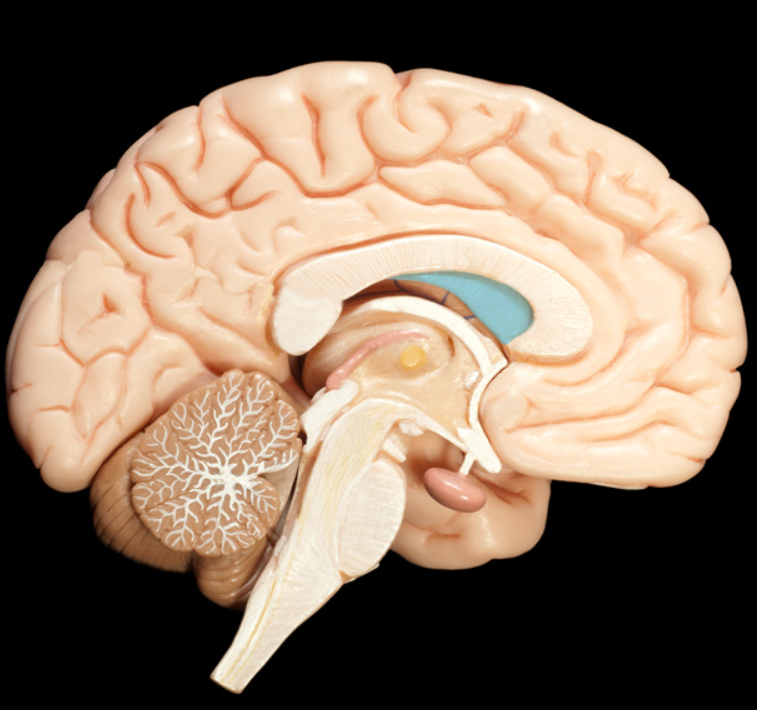

coverings of the brain and blood supply and Ventricles

lateral ventricles

third ventricle

fourth ventricle

cerebral aqueduct

choroid plexus

septum pellucidum